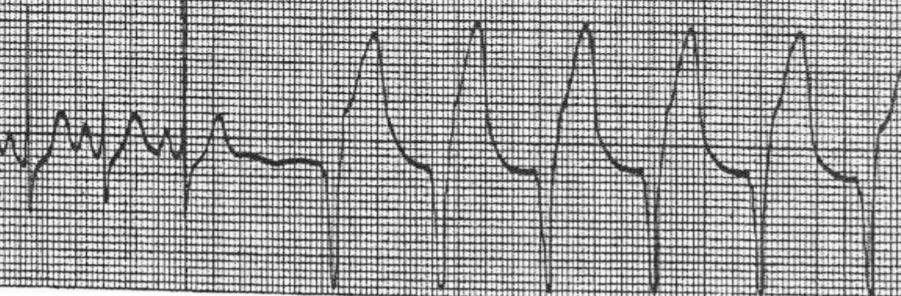

What is depicted by the EKG

Multifocal Atrial Tachycardia

What is depicted in the EKG

Atrial Fib